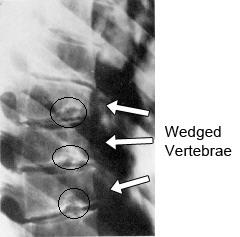

Κατά τον ακτινολογικό έλεγχο παρατηρούνται:

- Σφηνοειδής παραμόρφωση τουλάχιστον 3 συνεχόμενων σπονδύλων. Η σφηνοειδής παραμόρφωση των σπονδύλων θα πρέπει να είναι το λιγότερο 5 μοίρες για τον καθένα

- Αλλοιώσεις στις άνω και κάτω επιφάνειες των σπονδυλικών σωμάτων (irregular end-plates)

- Schmorl nodes (Όζοι του Scmorl). Οι όζοι του Schmorl είναι το αποτέλεσμα της διείσδυσης του πηκτοειδή πυρήνα στο σπογγώδες σπονδυλικό σώμα